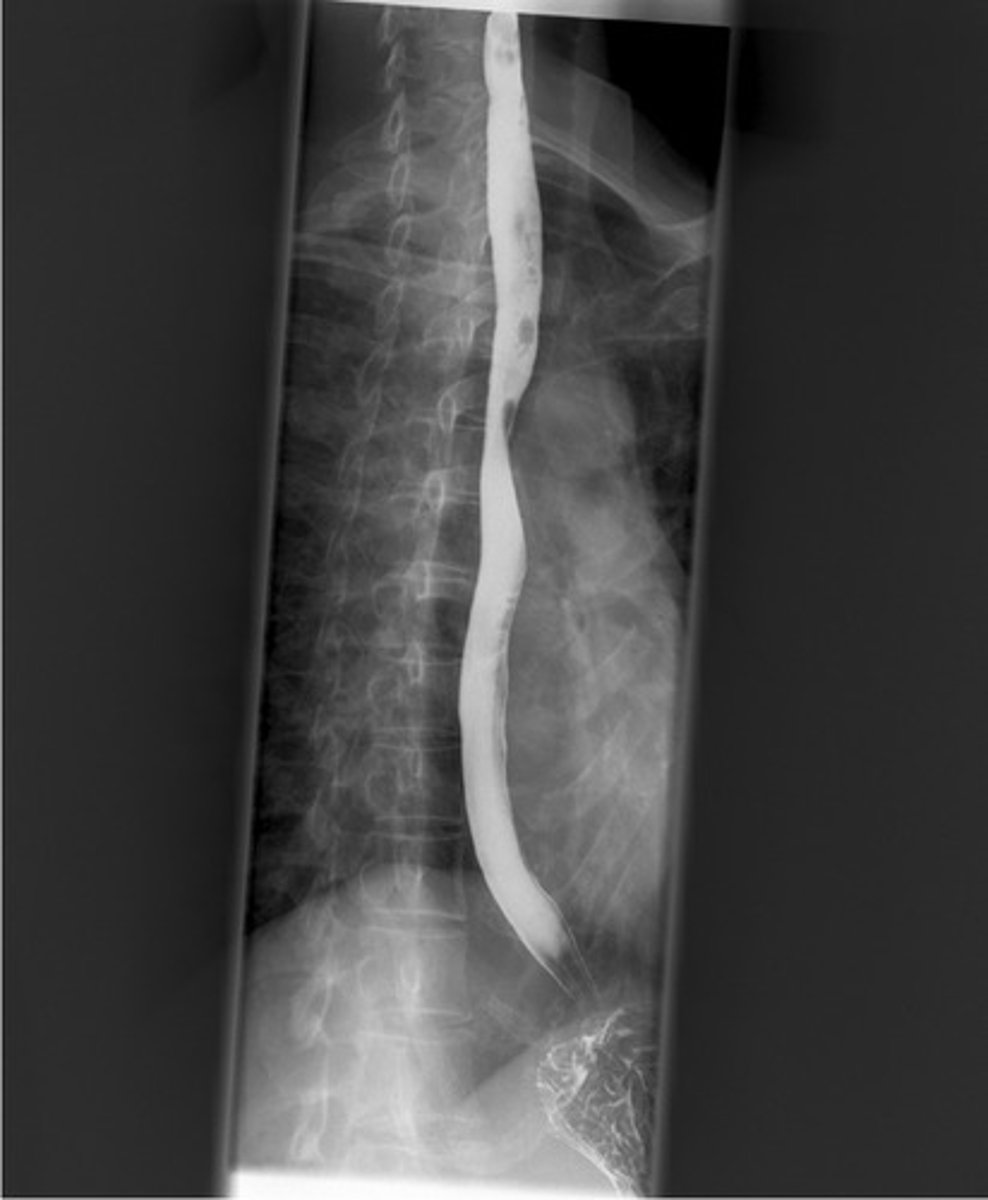

esophagus on barium swallow

Normal barium swallow

Normal barium swallow (pic 2)